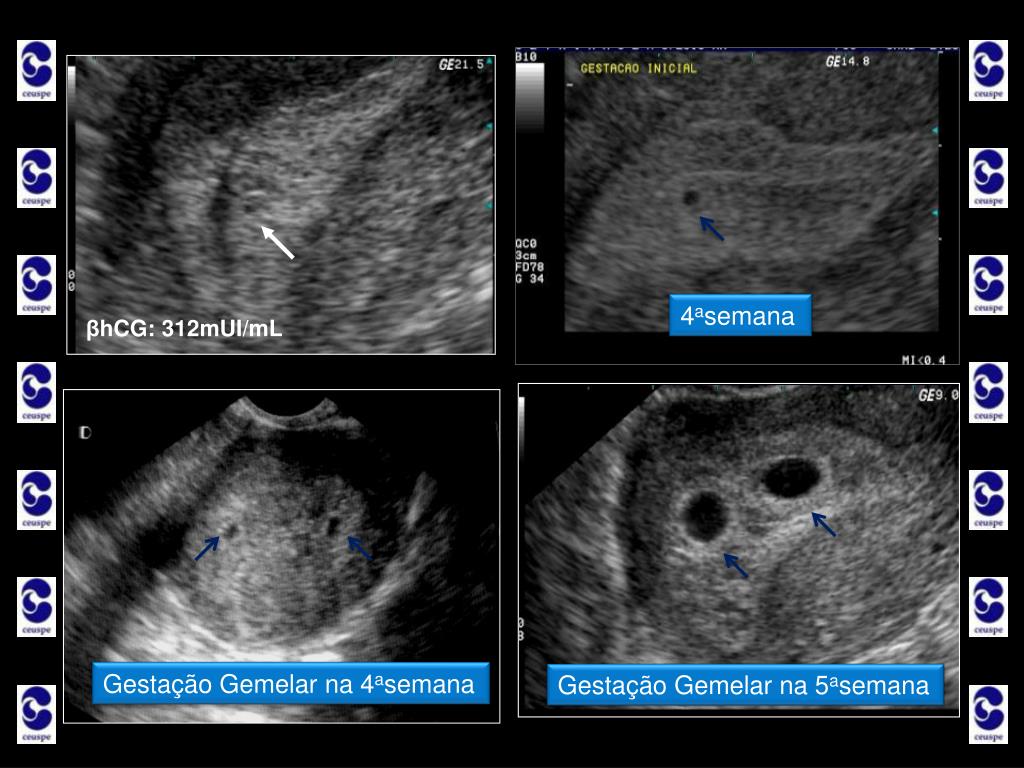

4. Ultrassonografia nos primeiros três meses Sua importância • Primeiro Trimestre • Idade Gestacional • um exame de sangue chamado beta-hCG confirma a gravidez; • a gestação começa a ser vista dentro do útero da mãe com um atraso aproximado de de 3 dias na menstruação, quando ela já tem uma idade de gravidez de 4 semanas e 3 dias na contagem do obstetra; • o exame de ultrassom no início é importante para termos a certeza de que a gravidez está dentro do útero, pois existem casos em que o saco gestacional se implanta fora do útero. Por exemplo, em uma das trompas da mulher;

5. Ultrassonografia nos primeiros três meses... • Primeiro Trimestre • Idade Gestacional • geralmente quando o exame de beta-hCG passa de 1.000mU/ml é possível encontrar o saco gestacional no interior do útero. Estamos então na quarta semana de gravidez; • dentro do saco gestacional, surge uma “bolinha” de líquido chamada vesícula vitelina que alimenta o pequenino embrião que ainda não é visível pela ultrassom, mas já está por lá! É como se essa “bolinha” fosse a estrela de Belém, que anuncia a chegada do novo ser! Já estamos na quinta semana; • na sexta semana, o embriãozinho surge com 5mm de comprimento piscando...É o pequeno coraçãozinho já batendo...

7. A gravidez é vista na ultrassonografia quando o teste de gravidez está acima de 800 a 1000 mUI/ml

8. 4asemana 4asemana Gestação Gemelar na 4asemana Gestação Gemelar na 5asemana βhCG: 312mUI/mL